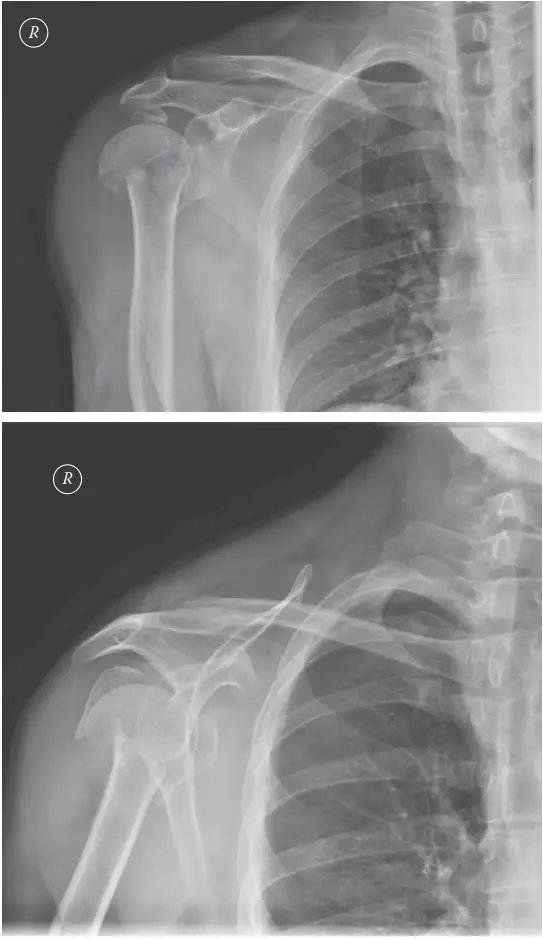

كسر عظم العضد القريب هو كسر يصيب الجزء العلوي من عظم الذراع بالقرب من مفصل الكتف، وينتج غالبًا عن السقوط. يبدأ العلاج بالتشخيص الدقيق عبر الأشعة، وقد يكون غير جراحي بالجبس أو جراحيًا بالصفائح والمسامير، ويوفر الأستاذ الدكتور محمد هطيف في صنعاء أفضل خيارات العلاج والتعافي لضمان استعادة الوظيفة.